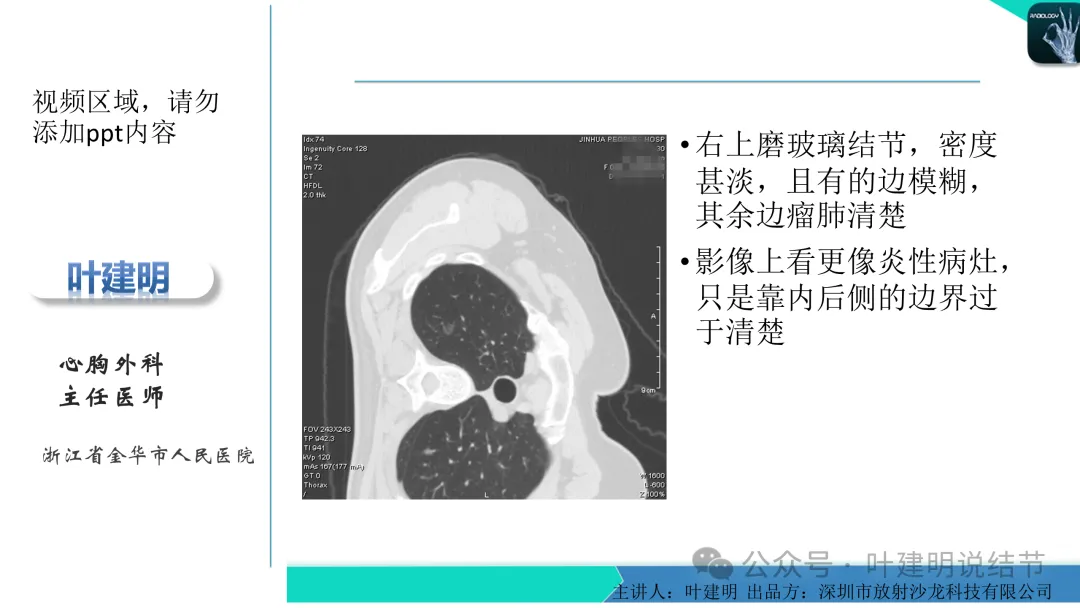

右上叶淡磨玻璃结节,才3-4毫米许,还很小,而且密度非常低,不过轮廓较清,边缘无膨胀性,像肺泡上皮增生。

左下叶结节,轮廓稍显模糊,邻近有血管走行,无血管弯征,病灶中间密度稍低,结节密度很淡,仅小片状模糊影似的。

右上叶与左下叶这两处结节均密度很低,非常淡,而且瘤肺边界并不是特别清晰,考虑少许肺泡上皮增生可能性大,目前没有什么风险,可常规年度复查随访。不能太着急,也不必太着急干预处理。我一直强调不要管最后病理是什么,而是从影像上判断风险如何、纯不纯,密度高不高,还能不能观察。你这种不单密度低,还小,不需要过分担心的,安心随访便可。意见供参考!

当地说考虑微浸润性腺癌的左下主病灶影像连续层面展示:

病灶出现,显模糊。

上图层面轮廓较清,但密度很淡,似见血管走行,但靠左前方的似条状磨玻璃密度与血管连着的到底是血管分支还是结节的一部分,其实并不确切。如果其实是血管分支,那病灶与它之间就不是空泡。

病灶在此层整体边缘显糊,灶内有空泡似的,瘤肺边界欠清。

边缘不平,还是灶内多发小空泡?邻近血管与之紧贴,但血管无异常走行。病灶密度很低,显糊。

中间所谓空泡更像是细支气管扩张,内壁非常光滑且圆形。

病灶边缘区淡而模糊。

这个病灶会是微浸润性腺癌吗?当然没有病理诊断,我也不能说百分之百必不会,但这样的病灶已经风险大到必得尽快手术切除干预了吗?显然还早着呢:1、影像不是典型的结节状;2、边缘与轮廓模糊不清;3、灶内似有细支气管扩张(更容易是细支气管扩张伴少许周围炎或肺泡上皮增生);4、血管邻近走但无牵拉影响;5、没有实性成分,没有锐利毛刺,没有胸膜牵拉,没有血管进入,没有任何倾向风险性高的影像特点。我一直强调:肺结节是否要干预处理,不要纠结于最后病理是什么,而要看风险高低;而风险高低的最重要术前判断依据一是随访有无进展,二是有没有实性成分。只要没有肉眼可见的影像上的实性成分,风险就是低的!何况病理也是人看的,原位还是微浸润,不典型增生还是原位有时也在一念之间。